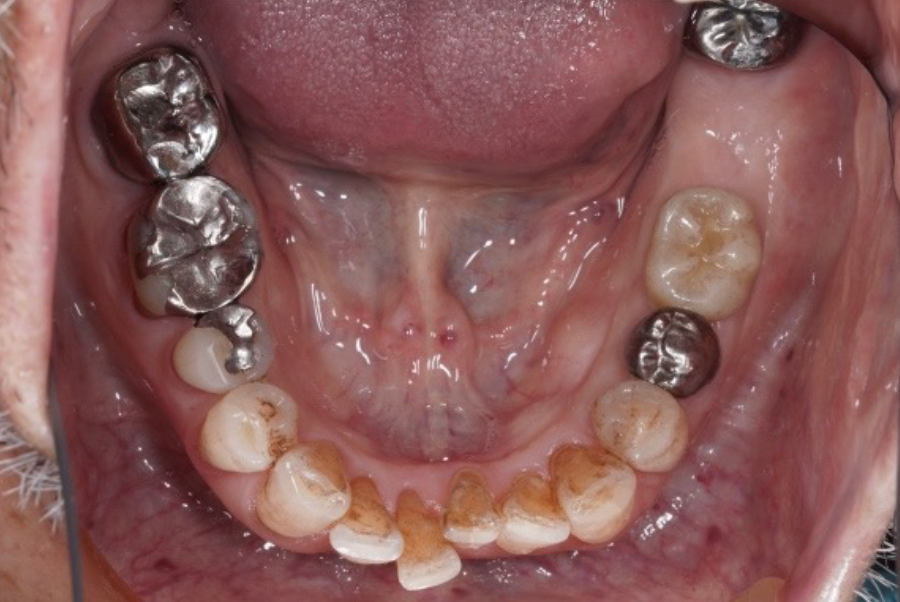

札幌駅前|

左下1本インプラント(6番)|

歯根破折・ブリッジ破損

からの回復症例

|80歳男性

- 治療内容

- CTによる精密検査を行い、骨量・骨質・神経位置などを詳細に評価した上で治療計画を立案しました。

抜歯後、左下6番にインプラントを1本埋入し、周囲の歯に負担をかけない形で機能回復を行いました。